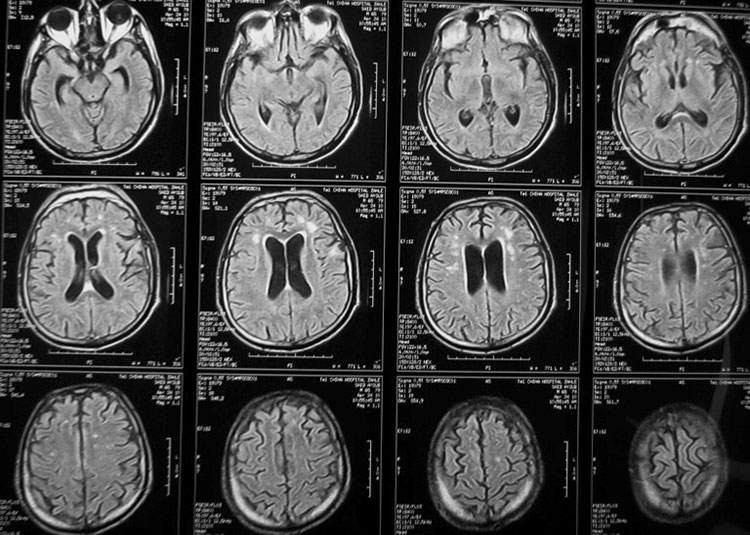

МРТ головного мозга помогает выявить серьезные патологии на самых ранних стадиях. Это могут быть аневризмы, опухоли, очаги демиелинизации. Также на МРТ хорошо видны аномалии развития головного мозга, анатомические дефекты, например, мальформацию Арнольда-Киари. Хорошо визуализируются на снимках послойно все структуры головного мозга, врач может с легкостью определить, нет ли у человек гидроцефалии, проблем с сосудами головного мозга. Для невролога практически незаменима томограмма, чтобы уточнить и подтвердить неврологический диагноз, потому что у многих болезней этой сферы очень похожие симптомы. Всего лишь за 20-30 минут исследования врач может получить неоценимую информацию о состоянии головного мозга пациента.

При этом МРТ может проводиться с контрастом и без. Контраст вводится в вену человека и начинает циркулировать по кровеносной системе, окрашивая хорошо сосуды на снимках. Необходимо контрастирование при подозрении на опухоли или для контроля лечения сосудистых патологий.